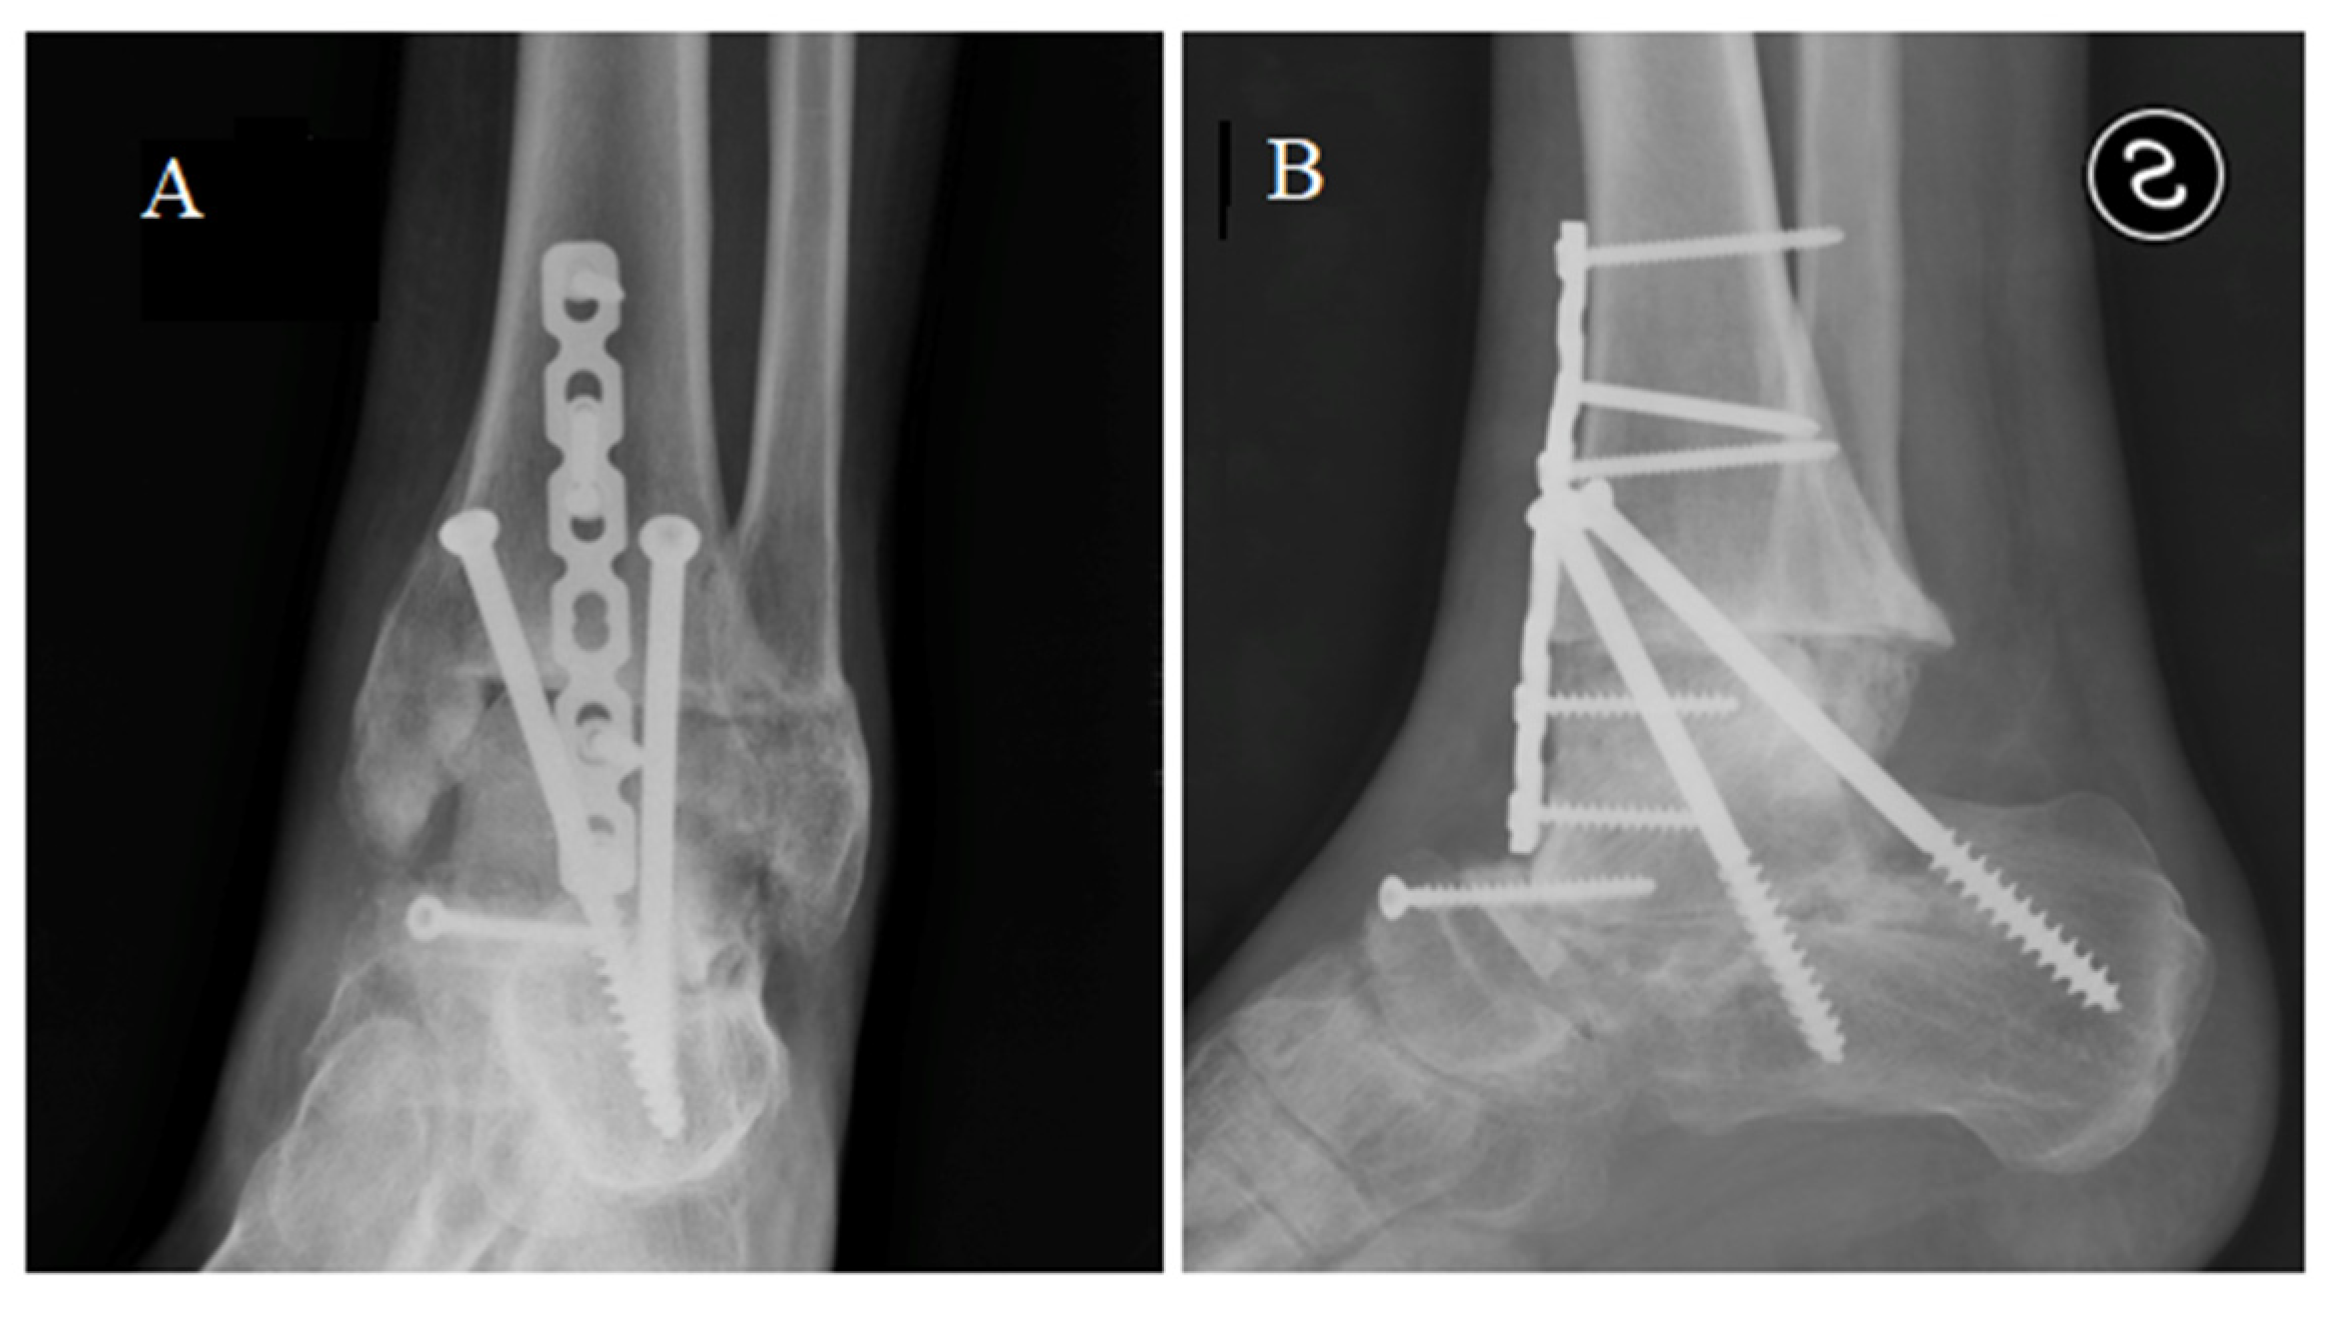

We proposed a tibial resurfacing, but the patient preferred a triple arthrodesis. Via anterior-medial access, the prosthesis was removed, and a fusion of the ankle, subtalar, and talo-navicular joint was performed with the use of a bone graft (Figure 6). At the last follow-up, 5 years after surgery, the patient was pain-free, wore normal shoes, and walked with a very slight limp. The AOFAS score was 81.

Figure 6.

X-ray in anterior posterior (A) and latero-lateral (B) projections showing the tibio-calcaneal arthrodesis.